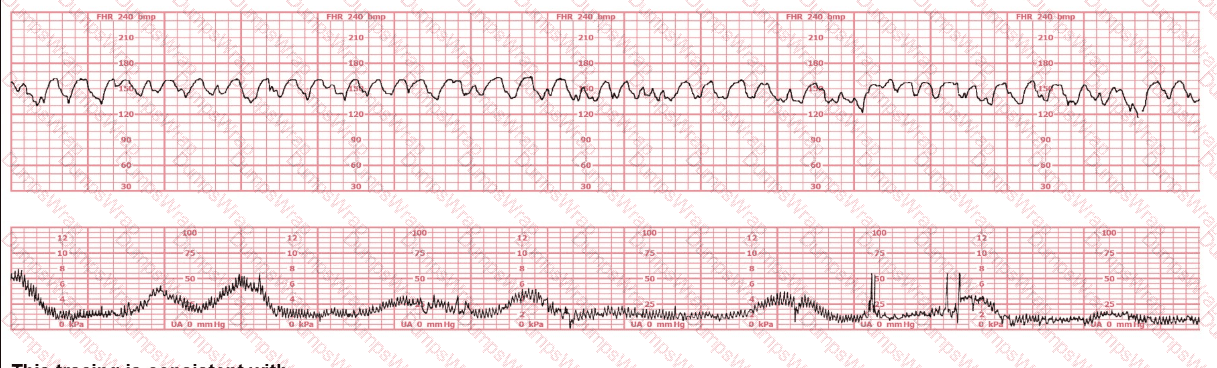

The decelerations seen in the fetal monitoring tracing shown are best described as:

Options:

Early

Late

Variable

Answer:

CExplanation:

Comprehensive and Detailed Explanation From Exact Extract–Based NCC C-EFM References:

Accurate classification of decelerations requires evaluating their shape, onset, nadir, recovery, relationship to contractions, and variability characteristics. NCC uses the NICHD standardized definitions, reinforced across AWHONN, Miller’s Pocket Guide, Menihan, Simpson, and Creasy & Resnik.

Key features in this tracing:

Abrupt onsetThe FHR drops rapidly from baseline to nadir in less than 30 seconds—this is the defining hallmark of a variable deceleration per NICHD.

Sharp V-shape and deep amplitudeThe tracing shows steep descents and ascents, characteristic of cord compression–type variable decelerations.

Inconsistent timing with contractionsThe decelerations do not begin at the start of contractions (as early decelerations would) and do not consistently begin after the peak of contractions (as late decelerations would). Variable decelerations can occur before, during, or after a contraction—exactly what is demonstrated here.

Rapid return to baselineAnother core feature of variable decelerations in NICHD/NCC definitions.

No uniform contraction relationshipEarly decelerations are symmetrical and mirror contractions. Late decelerations begin after the peak of the contraction. This strip does not match either pattern.

Differentiation per NCC-aligned definitions:

Early Decelerations:Gradual onset (>30 sec), nadir mirrors contraction peak, shallow, uniform.Not present.

Late Decelerations:Gradual descent, nadir after contraction peak, smooth shape.Not present.

Variable Decelerations:Abrupt onset (<30 sec), variable timing, sharp V-shape, rapid recovery, often with shoulders.Exactly matches the tracing.

Therefore, according to NICHD/NCC criteria, the decelerations shown are variable decelerations.

The pattern on the fetal heart rate tracing shown is likely due to

fetal head compression

placental insufficiency

umbilical cord compression

Comprehensive and Detailed Explanation From Exact Extract Sources:

The tracing demonstrates an abrupt-onset, sharp, V-shaped deceleration, occurring simultaneously with or slightly after a contraction—classic for variable decelerations, which are caused by umbilical cord compression.

According to AWHONN Fetal Heart Monitoring Principles & Practices, variable decelerations are defined by:

“Abrupt decreases in FHR below baseline of at least 15 bpm, lasting at least 15 seconds and less than 2 minutes.”

“Most commonly associated with umbilical cord compression, whether transient or recurrent.”

Physiology reference (Simpson & Miller, Pocket Guide):

Compression of the umbilical vein causes a brief acceleration.

Compression of the umbilical arteries triggers a vagal response, producing a rapid deceleration.

This creates the characteristic sharp ‘V’, ‘U’, or ‘W’ shape on the monitor.

Placental insufficiency (Choice B) produces late decelerations, which are gradual, not abrupt.

Fetal head compression (Choice A) produces early decelerations, which mirror contractions and have a gradual pattern.

Thus, the tracing is most consistent with variable decelerations caused by umbilical cord compression.